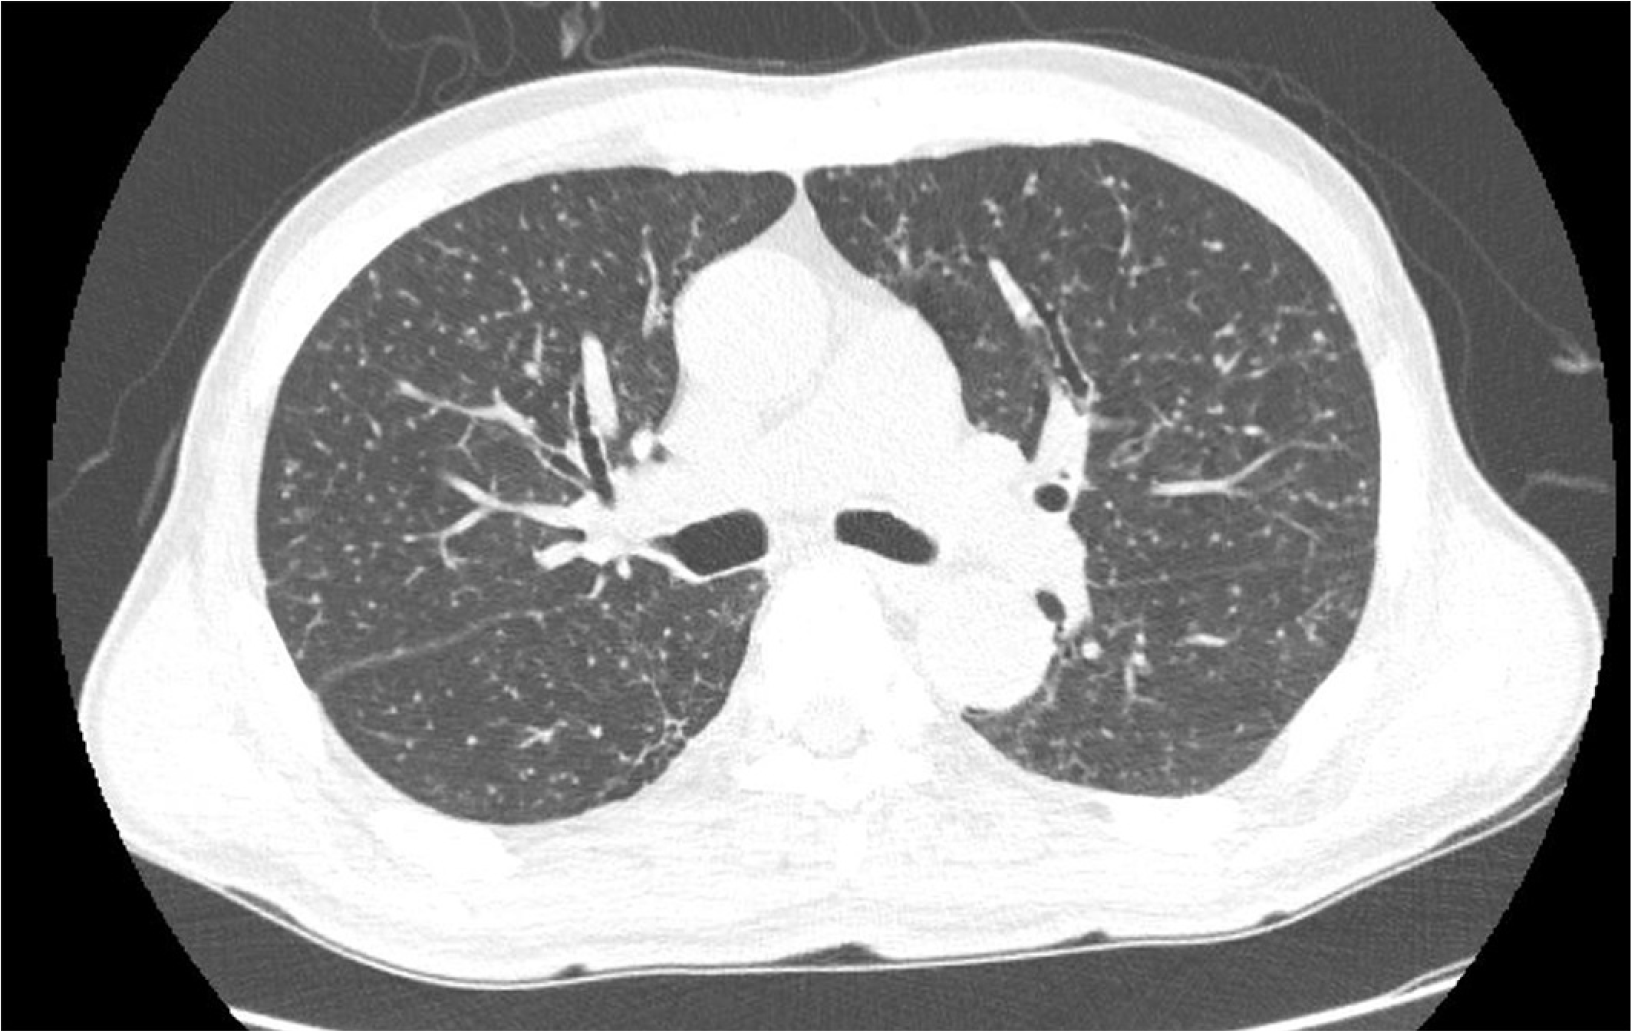

An ultrasound-guided liver biopsy was performed on the lesion in S3/4 of the liver. Histological examination revealed the presence of caseous granulomas and a negative acid-fast bacilli smear. However, the tuberculosis polymerase chain reaction (TB-PCR) was positive (Fig. 3). Further investigations included sputum analysis and chest CT, which confirmed the diagnosis of miliary TB (Fig. 4). Based on the initial presentation with isolated hepatic symptoms and subsequent development of miliary pattern, the patient was diagnosed with primary hepatic TB that later disseminated. He was initiated on a course of oral anti-TB medication. The regimen included isoniazid 300 mg, rifampicin 600 mg, ethambutol 1,200 mg, pyrazinamide 1,500 mg, and pyridoxine 50 mg to prevent peripheral neuropathy associated with isoniazid therapy. He is being monitored closely, and respiratory isolation measures have also been implemented.

Fig. 4

Numerous newly noted micro-nodules are present in both lungs, indicating miliary tuberculosis.